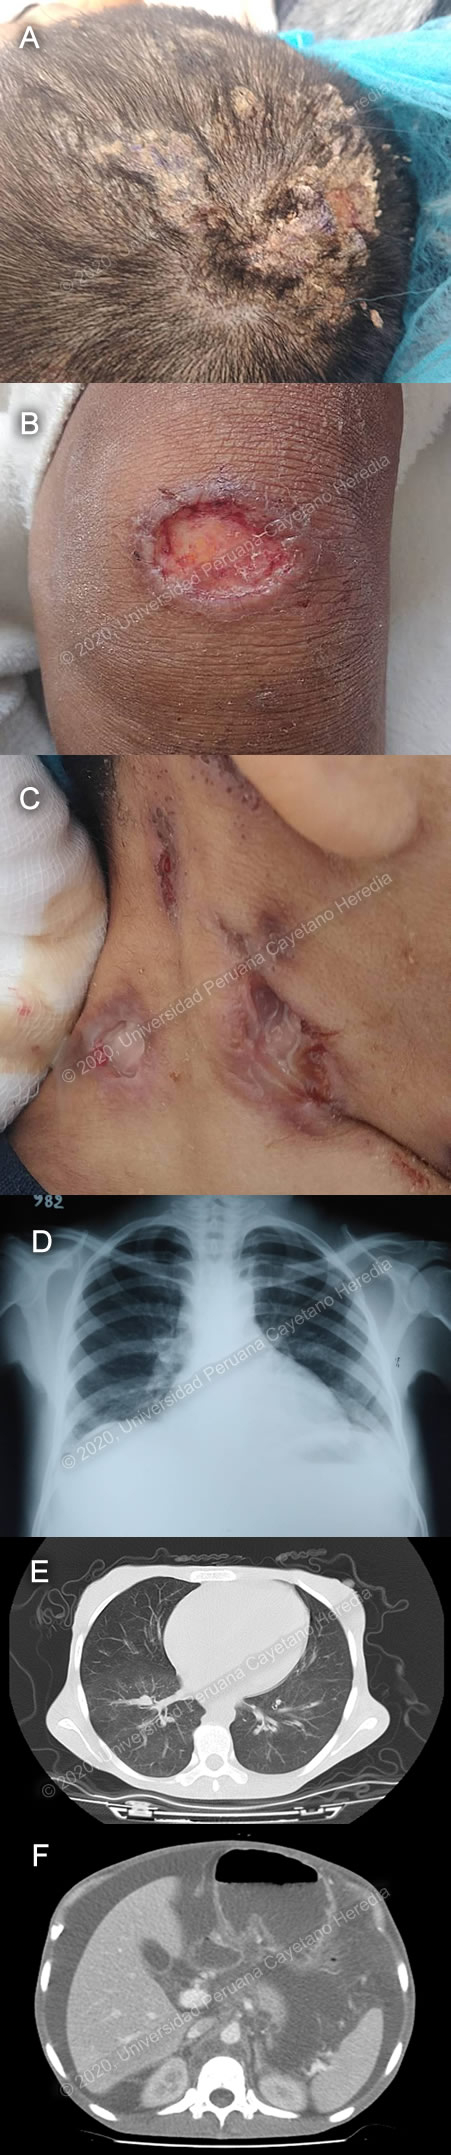

History: A 30-year-old female patient presents with a 6-month history of illness that presents with cervical, axillary and inguinal lymphadenopathies, malaise and weight loss. One month before admission, she notices something moving in her scalp. Two weeks prior to admission, she starts noting abdominal distention. Epidemiology: Born and lives in Manuquiari, La Convencion (Cusco), in the low jungle. Works as a homemaker and farmer. Part of the Matsiguenka native tribe. She is married. Denies previous illness. Denies any sick contacts. Physical Examination: BP:90/60, HR 86, RR 18, afebrile. Skin and mucosae were pale. Elevated desquamative plaque in parieto-occipital area of the scalp (Image A). Painless ulcerated lesion with well defined, elevated edges and a clean base, on left knee (Image B). Painful ulcerated preauricular, postauricular and cervical lymphadenopathies, approx. 2cm in diameter, with purulent discharge (Image C). Lung examination revealed bilateral diffuse crackles. Heart auscultation was significant for a mitral systolic II/VI murmur. The abdomen was very distended, bowel sounds were present, it was dull on percussion, with a positive wave sign, with no collateral circulation. The liver was firm and markedly enlarged, with no splenomegaly. Neurological exam was normal. Imaging StudiesChest x-ray showed a mild bilateral interstitial pattern (Image D). CT of the thorax revealed a bilateral fine ground-glass pattern, predominantly in bases, and mediastinal adenopathies (Image E). Abdominal ultrasound revealed an enlarged liver and abundant free fluid. Abdominal CT showed hepatomegaly, ascites and periaortic adenopathies (Image F). Laboratory: Hb: 6 g/dL; Hct. 22%; WBC 11 540 (neutrophils: 90%, eosinophils: 2.95%, lymphocytes: 4.07%); Platelets: 374 000. INR 1.4, PT 19.7, PTT 40.5. Gluc: 90 mg/dL, Urea: 39 mg/dL, Creat: 0.38 mg/dL, AST 15, ALT 10, GGT 15, Alk Phos 98, total bilirubin 0.23 (direct 0.07), LDH 196, albumin 2.1. AFB in sputum, urine, feces, lymphadenopathy secretion: negative. HIV and HBsAg were non-reactive. VDRL negative. Notes: Five different pathogens were isolated from this patient.

Diagnosis: Disseminated paracoccidioidomycosis, kerion (tinea capitis), myiasis, cutaneous leishmaniasis, intestinal hookworm infection.